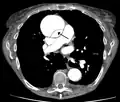

Computed tomography angiography is a fast, non-invasive test that gives an accurate three-dimensional view of the aorta. These images are produced by taking rapid, thin-cut slices of the chest and abdomen, and combining them in the computer to create cross-sectional slices. To delineate the aorta to the accuracy necessary to make the proper diagnosis, an iodinated contrast material is injected into a peripheral vein. Contrast is injected and the scan performed using a bolus tracking method. This type of scan is timed to injection to capture the contrast as it enters the aorta. The scan then follows the contrast as it flows through the vessel. It has a sensitivity of 96 to 100% and a specificity of 96 to 100%. Disadvantages include the need for iodinated contrast material and the inability to diagnose the site of the intimal tear.

Chest CT with descending (type B Stanford) aortic dissection (red circle)